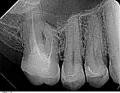

О возможности лечения или нет можно говорить только при наличии рентген-снимка.

Выложите его сюда на сайт либо запишитесь к нам на консультацию.